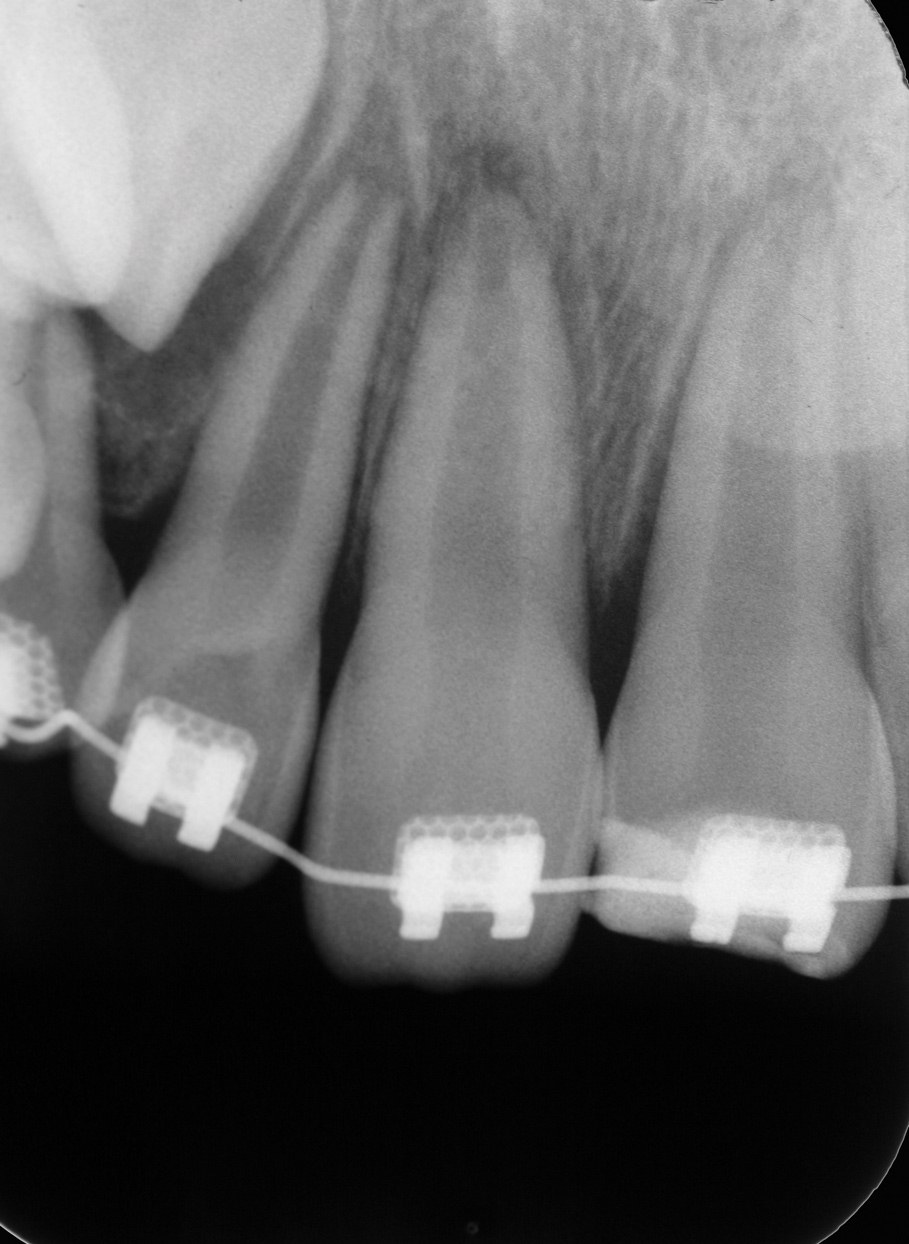

The patient's endodontic examination revealed a flexible splint from teeth Nos. 7 through 10 (Figure 1). Tooth No. 8 had a 3 mm x 3 mm class II fracture of the mesioincisal portion of the crown. Tooth No. 9 had a class IV fracture of the crown running labiopalatally from the remaining 2 mm of the crown to bone level on the palatal. A pulpotomy had been performed on the exposed pulp. Both teeth exhibited class III mobility. Teeth Nos. 7 through 10 did not respond to cold testing. None of the teeth were tender to palpation, and only tooth No. 9 had a slight positive response to percussion. Periodontal probings of tooth No. 8 were 4 mm to 5 mm on both the labial and palatal aspects. There was a narrow 12 mm probing on the straight palatal of No. 9; the remaining probing depths were 4 mm to 5 mm.2 A periapical radiograph showed both teeth Nos. 8 and 9 to have incompletely formed roots with wide-open foramina (Figure 2).

Fig 1. Age 8. Facial view of teeth Nos. 8 and 9 at initial examination.

Figure 1

Fig 2. Age 8. Radiograph of teeth Nos. 8 and 9 at initial examination.

Figure 2